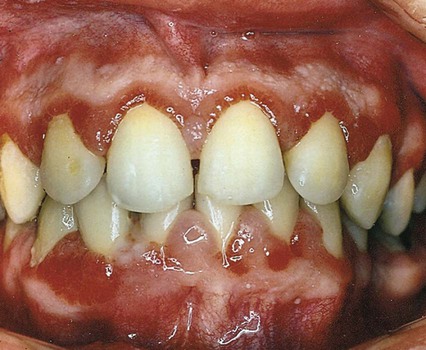

Gingivitis is inflammation of the gingival tissue. It may be the most common human disease and is one of the easiest to treat and control. Areas of redness and swelling characterize gingivitis, and the gingiva tends to bleed easily. In addition, there may be changes in gingival contour and loss of tissue adaptation to the teeth (Table 14-3).

Gingivitis is found only in the epithelium and in gingival connective tissues. No tissue recession or loss of connective tissue or bone is associated with gingivitis (Fig. 14-4). Other types of gingivitis are associated with puberty, pregnancy, and the use of birth control medications (Box 14-2 and Fig. 14-5). Orthodontic appliances tend to retain bacterial plaque and food debris, resulting in gingivitis (Fig. 14-6). Instruction regarding proper home care is a critical part of orthodontic treatment (see Chapter 60).

Gingivitis is painless and often remains unrecognized until a dental professional emphasizes its importance. Improved daily oral hygiene practices may reverse gingivitis.